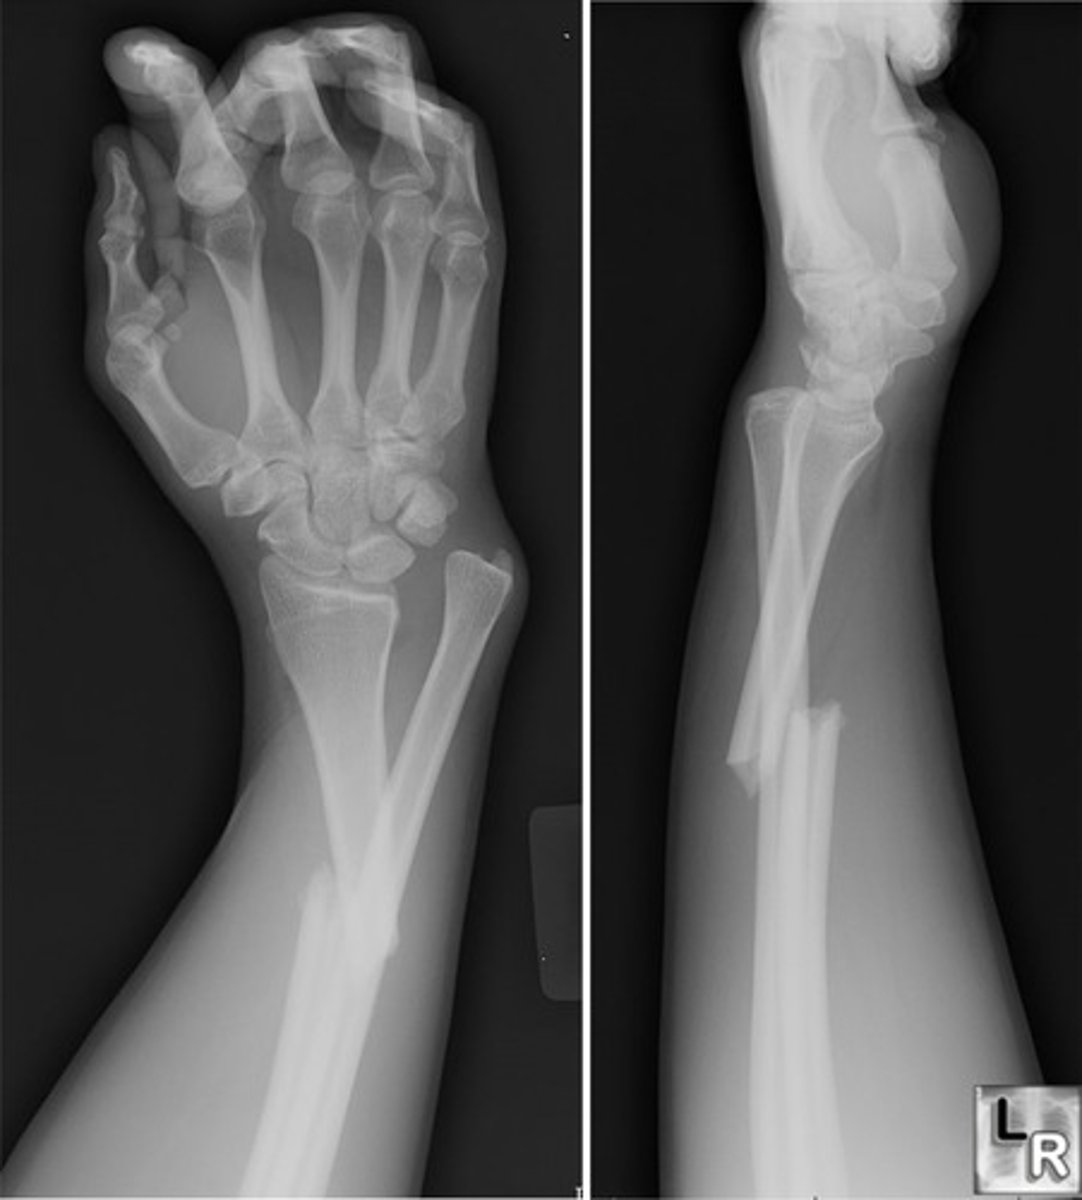

FOOSH: what type of fracture will occur from falling forward and landing on an OUTSTRETCHED hand?

Colle's fracture (distal radius)

FOOSH: what type of fracture will occur from falling forward and landing on an FLEXED wrist?

Smith's fracture

FOOSH: what type of fracture will occur landing on an outstretched hand with elbow locked?

supracondylar fracture with elbow dislocation

FOOSH: what TWO types of fracture can occur when landing on an outstretched hand with hyperpronated forearm?

Monteggia fracture

Galeazzi fracture